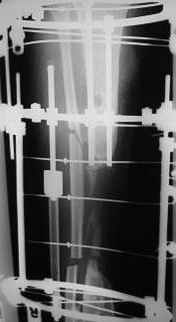

Re: bone defect

Dear Dr. Firas

You can do it like this also...